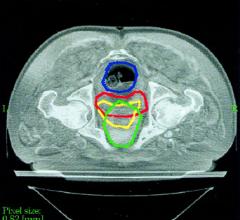

January 20, 2010 - Cervical cancer is the second most common cancer in women worldwide. Treatments for the disease have ...

The radiation therapy channel covers all aspects of radiation oncology technology. Radiation therapy includes linear accelerators (LINAC), proton therapy, brachytherapy, image guided radiation therapy (IGRT), focused ultrasound, stereotactic body radiation therapy (SBRT), intensity modulated radiation therapy (IMRT), treatment planning systems and tomotherapy.